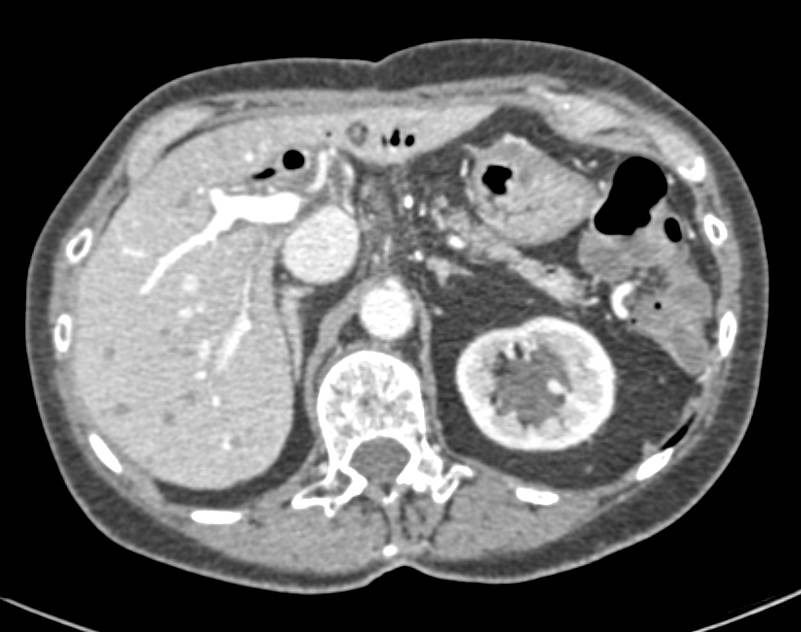

Neuroendocrine Tumor Near Head of Pancreas